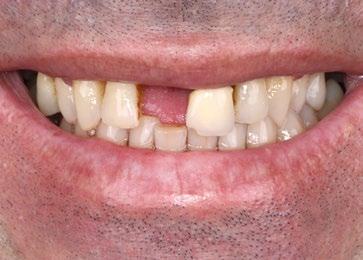

Fotos iniciales que muestran claramente el grave compromiso de la arcada superior debido a la enfermedad periodontal. Giovanni Zucchelli Alessandro Zucchelli Pietro Bellone

Se presenta el caso de un paciente varón de 48 años de edad, ASA II, fumador que acude a consulta por la pérdida de su incisivo central superior derecho (Figura 1).

A la exploración clínica se observa enfermedad periodontal estadio III grado B con múltiples ausencias dentarias posteriores de larga evolución que han ocasionado la migración de los dientes adyacentes y antagonistas generando múltiples prematuridades e interferencias. Como consecuencia de todo ello, el paciente ha perdido el diente 1.1 con pérdida de volumen de tejido y el 2.1 presenta movilidad grado III con pronóstico imposible (Figura 2).